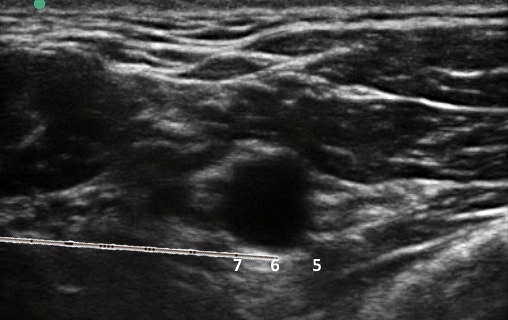

One cadaver dissection showed less dye surrounding the medial and lateral cords than the posterior cord when using a retroclavicular approach.[18] However, as mentioned previously, a randomized trial found similar rates of sensory and motor block success, surgical success, supplementation, and analgesic use.[6] To maximize perivascular spread during a retroclavicular approach, we suggest using our 5-6-7 technique.[5] Advance the needle past the 6-o’clock point to the axillary artery as viewed in the ultrasound image. At 5-o’clock (posterocaudal) position, deposit 25% of the local anesthetic. Withdraw the needle and deposit 50% of the local anesthetic at the 6-o’clock position and 25% at the 7-o’clock position (Figure 6).